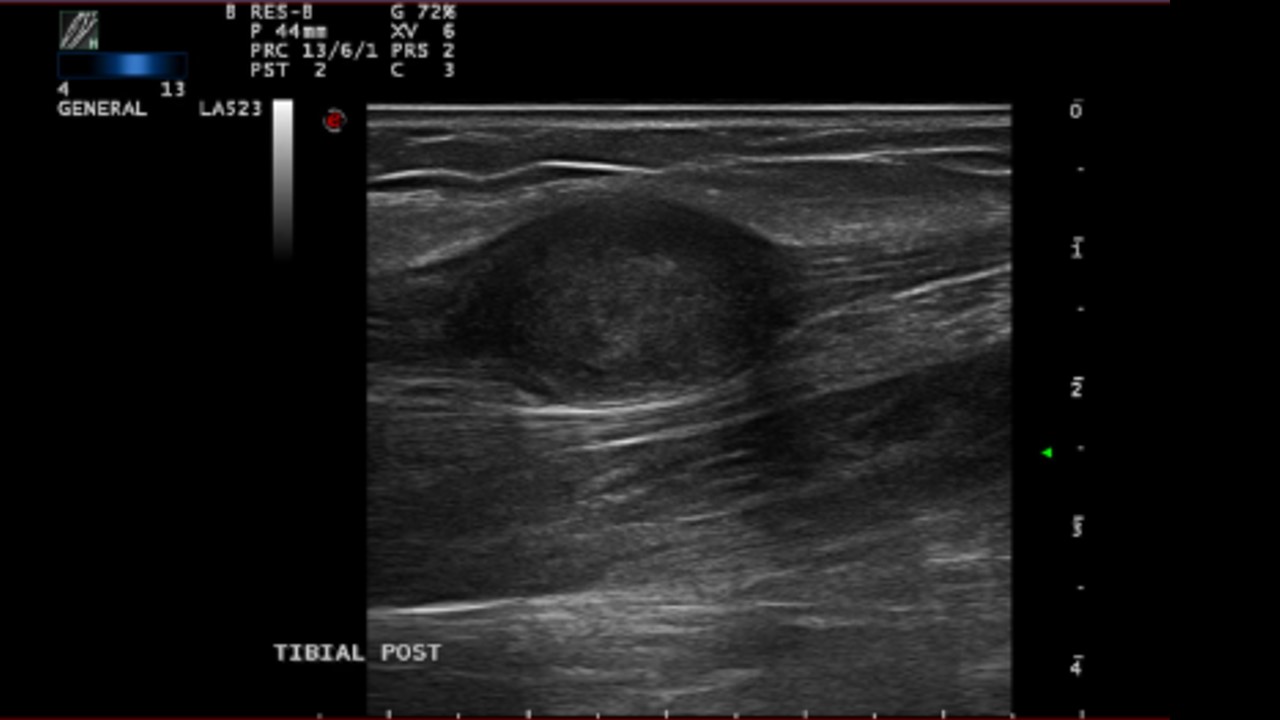

2018 Ecografía reglada: tumoración de 2,4 cm. Impresión diagnóstica: Neurilemoma dependiente del nervio tibial posterior. Plan: biopsia de lesión.

2025 Ecografía reglada: nódulo sólido hipoecogénico, bien delimitado de 2,5 x 1,4 cm.

Ecografía de control a los 7 años en la que no se aprecia crecimiento de la lesión por lo que la lesión impresiona de tumoración benigna de morfología estable.

Seguimiento ecográfico periódico, valorar cirugía curativa si dolor.